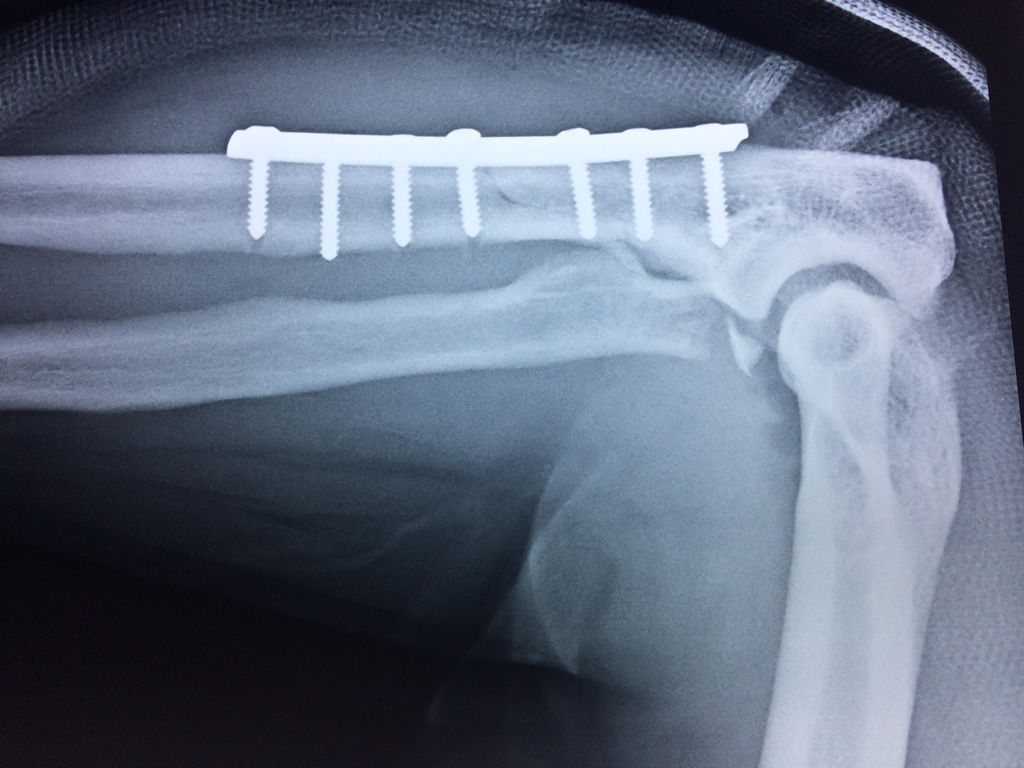

Los extremos óseos se conectan entre si por un conjunto de ligamentos que contribuyen a su fijación y están rodeado por una estructura común que se llama cápsula articular, en cuyo interior se encuentra el líquido sinovial.